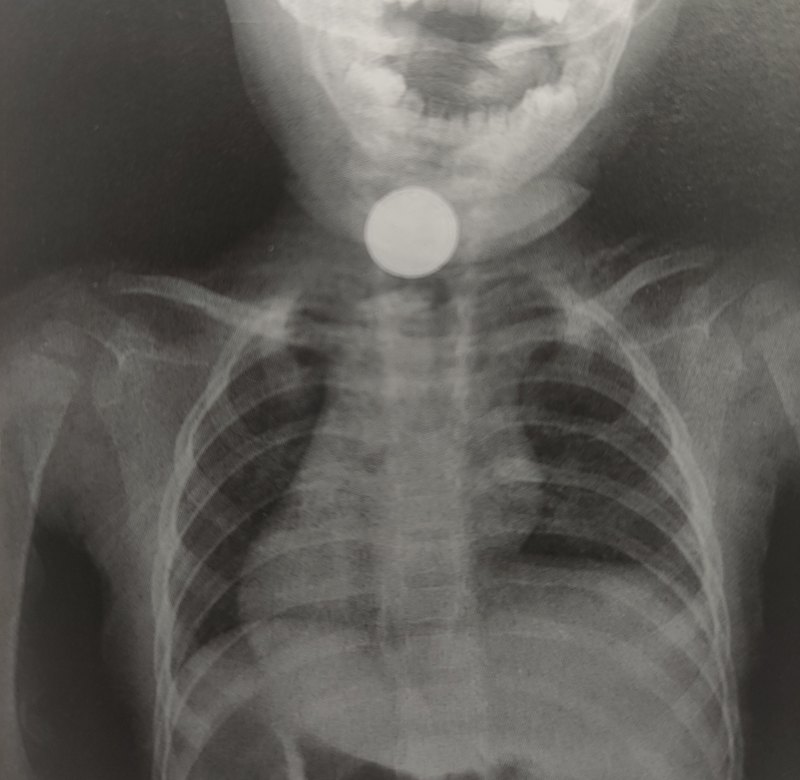

今天的一臺(tái)食道異物(紐扣電池),一歲多的小寶寶異物卡了10多個(gè)小時(shí),手術(shù)中發(fā)現(xiàn)食道已經(jīng)被燒壞、碳化,后續(xù)孩子可能會(huì)有食道狹窄、消化道出血、穿孔等風(fēng)險(xiǎn)……預(yù)防重于泰山?。?!一定要讓小寶寶們遠(yuǎn)離危險(xiǎn)的紐扣電池?。。?